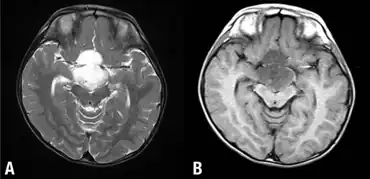

Diencephalic syndrome, or Russell's syndrome is a rare neurological disorder seen in infants and children and characterised by failure to thrive and severe emaciation despite normal or slightly decreased caloric intake. Classically there is also locomotor hyperactivity and euphoria. Less commonly diencephalic syndrome may involve skin pallor without anaemia, hypoglycaemia, and hypotension.[1] The syndrome is a rare but potentially fatal cause of failure to thrive in children. Failure to thrive presents on average at 7 months of age.[1] Of note the syndrome is not associated with developmental delay.[2] There may be associated hydrocephalus.

Diencephalic syndrome was first described by Dr. A. Russell in 1951.[3] It is usually caused by a brain tumor such as a low-grade glioma or astrocytoma located in the hypothalamic-optic chiasmatic region.[1] It is not yet understood how diencephalic syndrome causes the effects on appetite and metabolism which are seen, though inappropriately high growth hormone release has been proposed,[4] as has excessive β-lipotropin secretion[1] and overall increased metabolic demand.[5] It is treated with nutritional optimisation while the underlying lesion is treated with chemotherapy, surgery or radiotherapy.